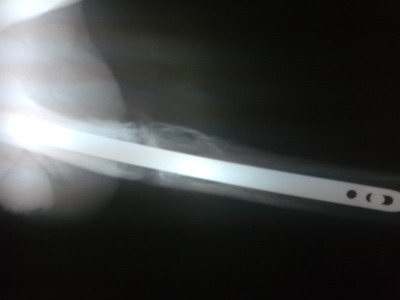

Radiografías con enfoque en fisiatría

Envíado por Dr. Hernán Darío Sánchez Ramos